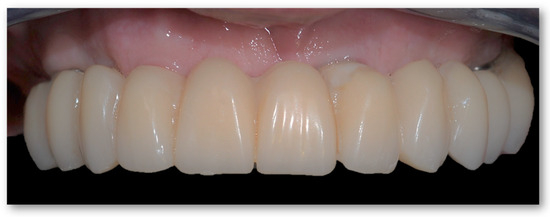

2.2. Second Step: From FDP to Implant-Supported Overdenture